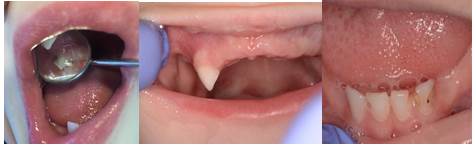

Las restauraciones dentarias fueron realizadas con cemento de ionómero de vidrio de fotocurado (FUJI IX GC Corporation) en las piezas 53, 71, 72, 81 y 82 (Figura 6). Las prótesis removibles superior e inferior para mantenimiento del espacio se confeccionaron siguiendo correctamente los pasos de su confección: a) toma de impresiones con silicona pesada y liviana en un solo tiempo y vaciado para la obtención de modelos de yeso, b) placa de registros y rodetes, c) registro oclusal y restablecimiento de dimensión vertical, d) enfilado dentario, e) prueba de dientes y f) prótesis removible superior e inferior (Figuras 7, 8, 9,10, 11, 12 y 13).

Figura 7 y 8: Toma de impresiones con silicona y obtención de modelos y placa de registros y rodetes